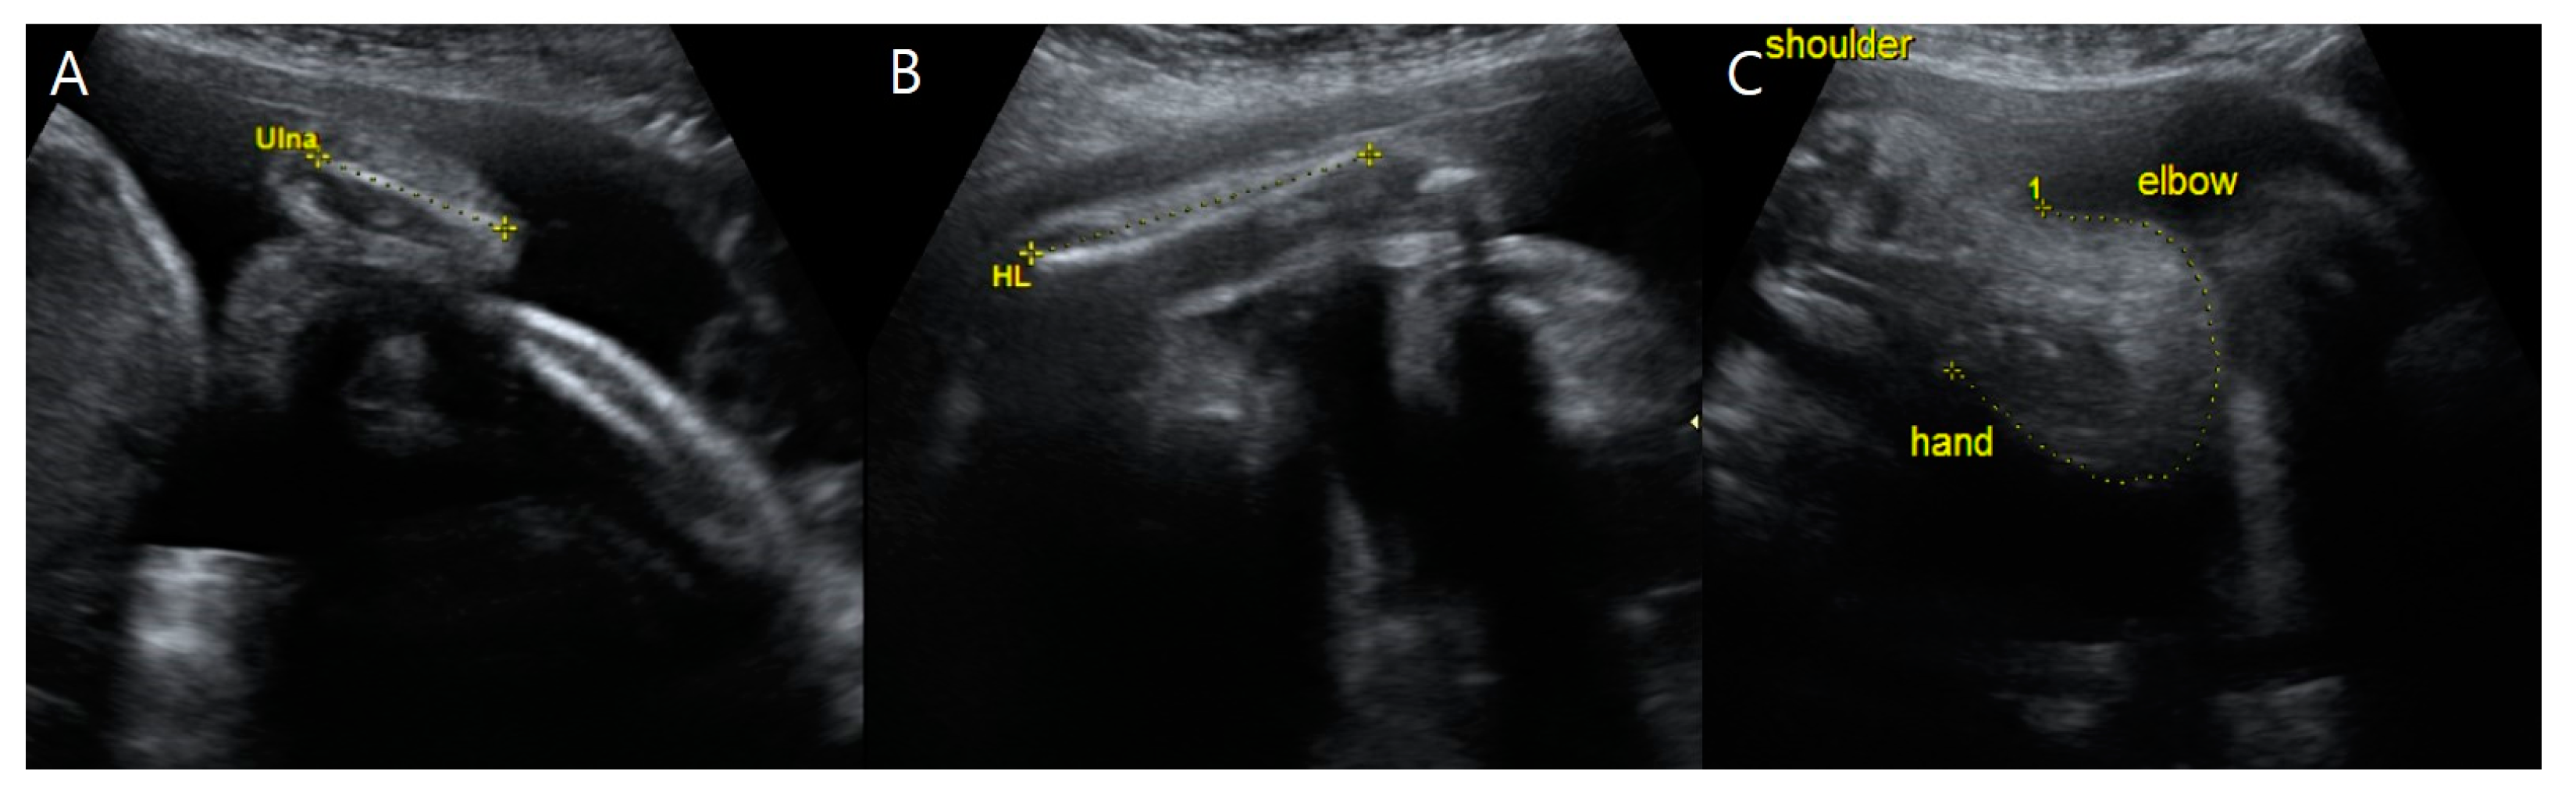

A detailed sonographic examination of fetus A detected a bilateral absence of the radii and thumbs (Figure 2). Both hands deviated in the direction of the absent bone, leading to an abnormally curved posture and radial clubhands. For the right forearm, we could not find the humerus because there was only one long bone proximally adjacent to the shoulder and distal to the curved hand.

At 34 + 0 weeks gestation, an emergency cesarean delivery was performed because of relapsed preterm labor. The first baby was a male with VACTERL-H association, weighing 1390 g, and the second baby was a healthy female, weighing 1890 g. The Apgar scores at 1 and 5 min were 6 and 8 in the first twin baby and 5 and 8 in the second twin baby. The first twin had multiple anomalies diagnosed prenatally. Related imaging studies were performed, including an infantogram and 3D CT (Figure 8, Figure 9, Figure 10, Figure 11 and Figure 12). A cardiacangio 3D CT revealed dextrocardia of embryonic arrest with pulmonary hypoplasia and a tracheoesophageal fistula with a right bronchus (Figure 8). The infantogram and 3D CT showed upper-limb agenesis, which aligned with the prenatal diagnosis, including aplasia of the right proximal humerus, radial hypoplasia, and hypoplastic thumb (Figure 9, Figure 10 and Figure 11). The first twin baby also had an imperforate anus and colon dilatation (Figure 12). Neonatal echocardiography showed dextrocardia with right atrial enlargement and an interrupted inferior vena cava without major congenital cardiac abnormalities. The findings from postnatal imaging supported the prenatal diagnosis of a VACTERL-H association. On his fifth day of life, the twin baby with the VACTERL-H association died.

According to the literature, a detailed examination of the upper limbs in the first-trimester screening may be useful for detecting familial VACTERL-H cases. Approximately 40–50 percent of VACTERL-associated patients had limb malformations such as thumb aplasia or hypoplasia, polydactyly, and lower-limb anomalies [15,16]. We detected upper-limb anomalies, including radial aplasia, syndactyly, and clubhands, on prenatal ultrasound examinations. It is important to evaluate the length, shape, and movement of long bones, including the radius, ulna, tibia, and fibula, as well as the femur and humerus.

Figure 2. Upper-limb anomalies of fetus A on ultrasonography at 31 + 3 weeks gestation. (A) The length of fetus A’s ulna was 2.63 cm (<5th percentile). (B) Fetus A’s humeral length was 4.63 cm (<5th percentile). (C) Fetus A’s forearm with the absence of radii, thumbs, and radial clubhands, or abnormally curved hands toward the absent bone.